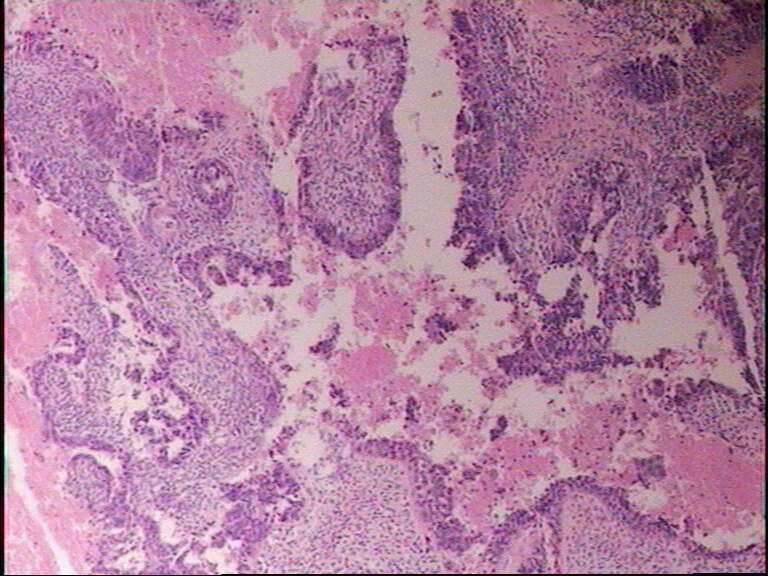

男77岁,肘窝肿物20天

关节附近恶性肿瘤,双向分化,滑膜肉瘤?标记。

关节附近恶性肿瘤

恶性肿瘤,做免疫组化。